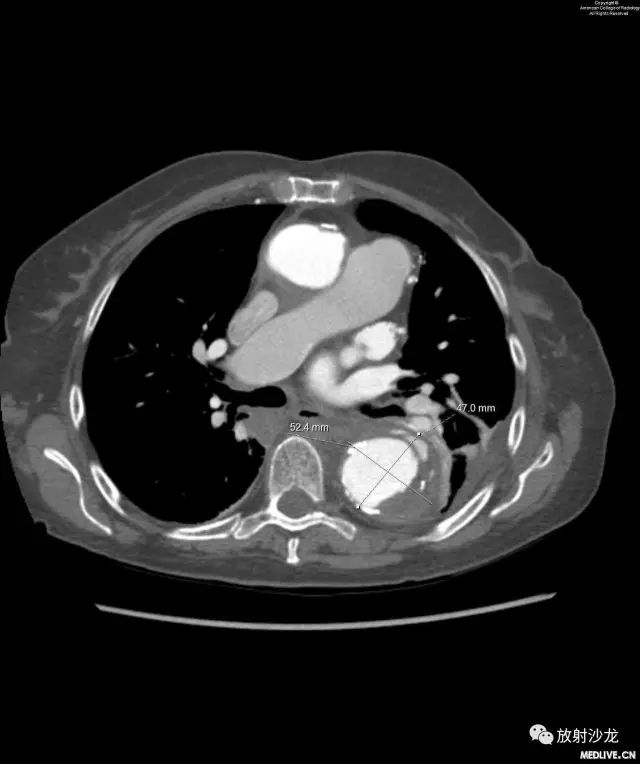

图7和图8:图7与图6为同一层面的图像。该患者恢复4周后再次出现新的胸痛。降主动脉扩张区可见假腔内血栓形成和慢性附壁斑块。图8与图6情况相似,额外补充了测量数据。

在血管手术前一周,患者诉10/10级剧烈胸痛,急性发作使她从睡梦中惊醒。影像学检查显示假腔内血栓形成、受累部位主动脉瘤样扩张、顽固左侧胸腔积液。患者进行了成功的血管内支架治疗。